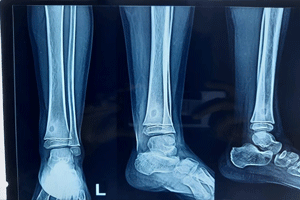

Trauma-Fractures in children

As parents, we know an active child is a happy child, but this can sometimes lead to bone injuries. According to Dr. Rohit Jain, a leading sports injury specialist and pediatric orthopedic doctor, fractures are common, especially in children who engage in sports or rough play.

Types of Fractures:

• Greenstick Fractures : Partial breaks that bend rather than completely shatter.

• Compound Fractures : Bones that break through the skin, requiring immediate care.

• Transverse Fractures : Horizontal breaks often from direct impact.

• Comminuted Fractures : Bones shatter into several pieces, typically from high-impact activities.

• Stress Fractures : Small cracks due to repetitive stress, common in athletes.

Effective Treatment Options

For minor fractures, we use advanced non-surgical methods and specialized plasters to aid healing. In more severe cases, Dr. Jain may recommend surgery for better recovery. Don’t let a fracture hinder your child’s active lifestyle! Contact us today.